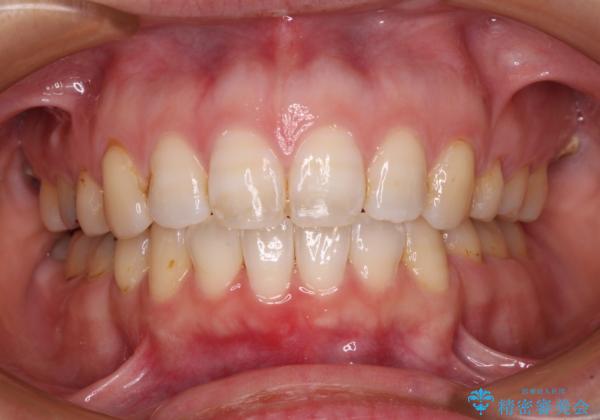

- 口元の閉じにくさと、前歯のでこぼこの歯並びを気にして来院された患者様です。

口元を積極的に引っ込めるために、上下左右の小臼歯計4本を抜歯することとしました。

セオリーでは第一小臼歯を抜歯しますが、上下右側は第二小臼歯に銀歯が装着されているため、第二小臼歯を抜歯することとしました。

上下正中を左右対称に揃えるため、アンカースクリューや補助装置を使用しながら口元を下げていくこととしました。

積極的に前歯を牽引したことで、口元の閉じにくさは顕著に改善され、横顔のシルエットが大幅に変化しました。